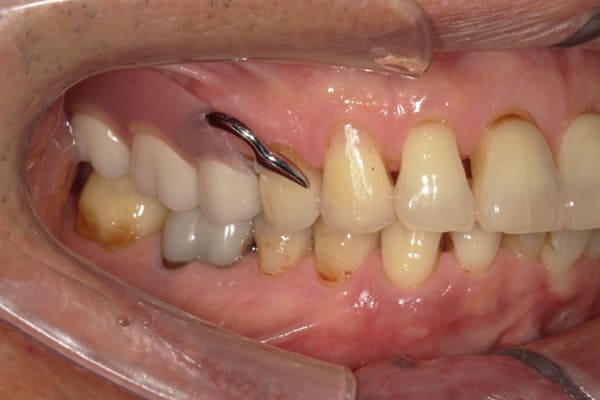

症例レポート[CASE.02]

入れ歯がカパカパして痛い、

歯がぐらぐらする

- 性別・年齢

- 男性(60代)

- 主訴

- 入れ歯がカパカパする、歯がぐらぐらして痛い、食いしばれない

- 治療

-

- 上顎精密総金属床総入れ歯

- 下顎精密金属床部分入れ歯

- ジルコニアクラウン4歯

- 治療期間

- 約3か月間

- 費用

- 上顎精密総金属床総入れ歯:55万円

- 下顎精密金属床部分入れ歯:55万円

(ミリング、ラベット加工込み) - ジルコニアクラウン:11万円×4歯

合計:154万円(税込)

上の前歯が重度歯周病により動揺し、残せない状態のため、入れ歯も動揺がありました。

ご自身の歯に負担の少ないバネ、また見た目も改善

バネをかける歯は繋げることで強度を増し、歯への負担を軽減し、歯の寿命を長くする設計へ。

バネがかかる歯の被せ物は、歯への負担を減らし、入れ歯が動きにくいようになる形態をあらかじめ付与することで、より入れ歯の機能が高まります。

治療を行う際、被せ物や入れ歯は、別々に考えるのではなく、一口腔単位としてお口全体のことを考え最良の治療計画を立てることが歯の寿命、機能効果を向上させるため、専門医としてこのことは常に心掛けて治療を行っています。